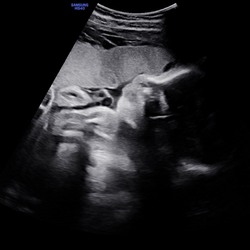

Je ziet je buik heel regelmatig zachtjes op en neer gaan, als een (redelijk snelle) ademhaling. Maar het is niet je eigen ademhaling. Als je even je adem inhoudt kan je dat goed zien. Ik kan helaas geen filmpje bijvoegen hier, anders kon ik het laten zien..🥰

oh de hik eigenlijk? ja dat heeft ze al sinds 28 weken, heel bijzonder 🥰

Nee niet de hik. Die komt met tussenpozen, kleine plopjes. Die voel ik ook 1 a 2x per dag😅 Het oefenen met ademhalen is hetzelfde als wij met lucht ademhalen. De baby doet dit echter met vruchtwater. Deze beweging voelt meer als golfjes. Je kunt het evt googlen of Chat gpt vragen :)